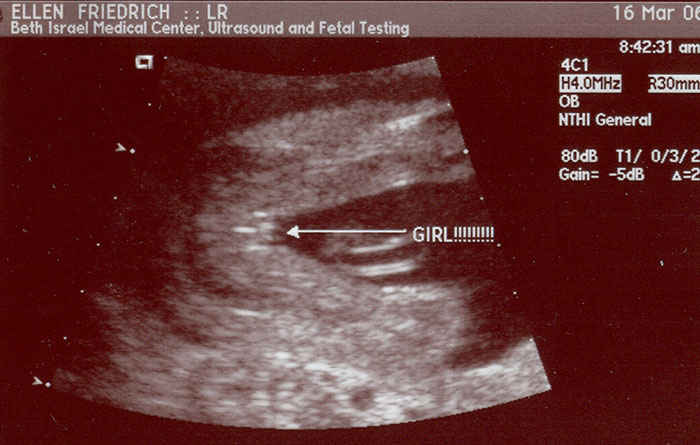

Making progress - 20 weeks- March 16 - 2006

Evidence of a girl